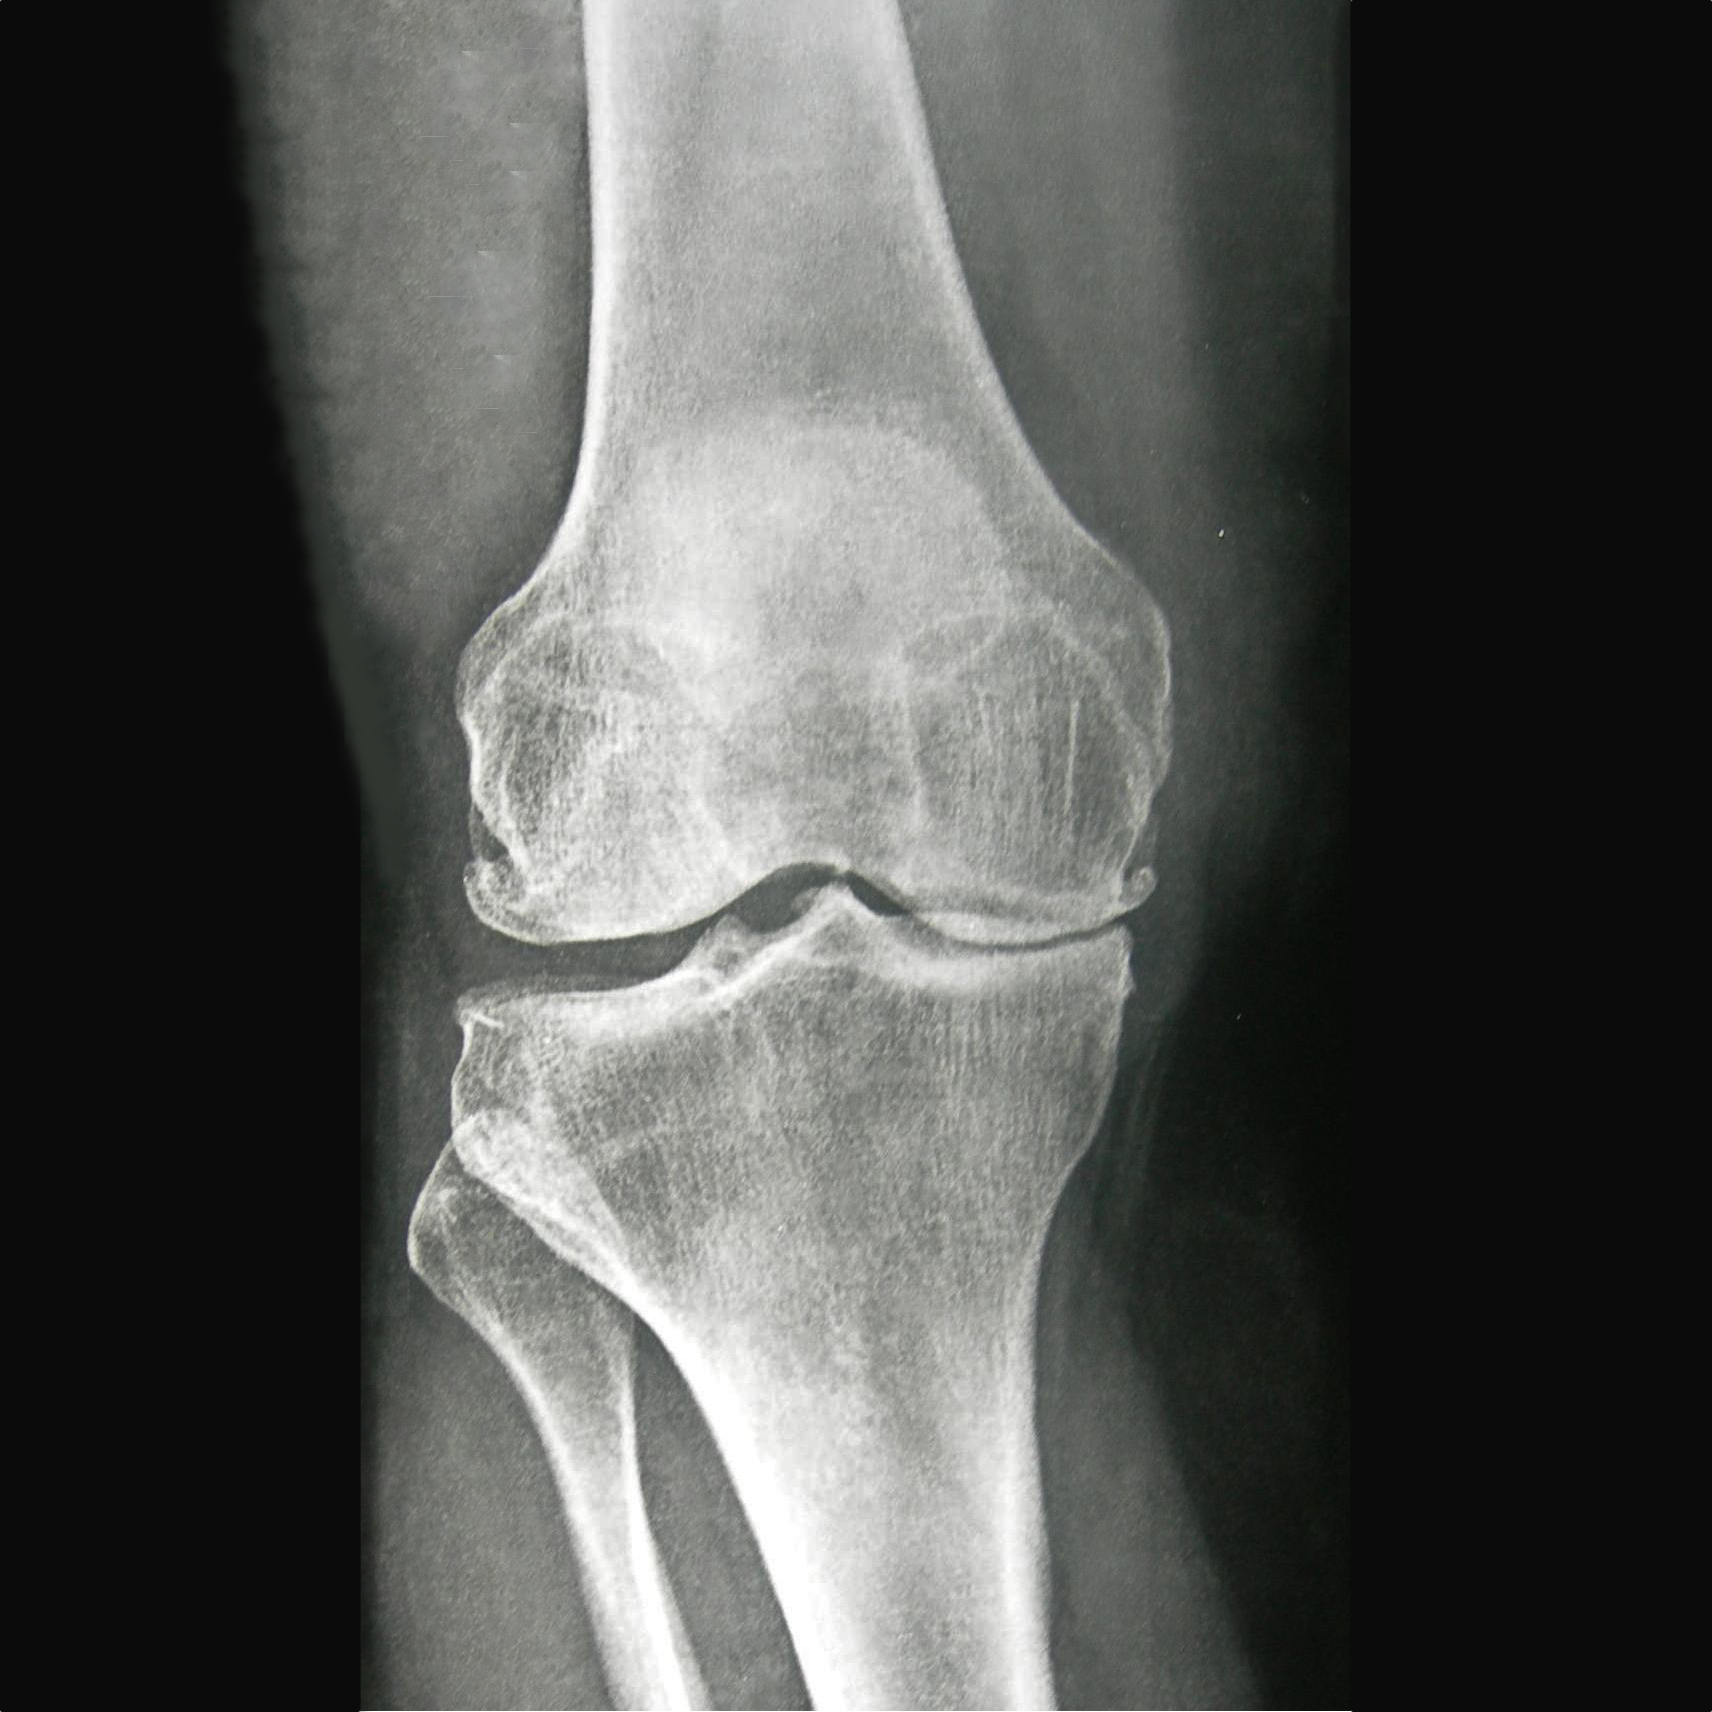

Reading X-Rays

The articular cartilage and meniscus cannot be seen on an X-ray image. An X-ray of a healthy knee with good cartilage should show a gap between the bones, such as the knee on the right of this image.

You can see that there is no gap between the bones of the knee on the left of the image. This indicates the articular cartilage and meniscus have completely worn away causing arthritis and the ends of the bones to rub. This is a painful condition.

This X-ray shows cartilage wear in the medial compartment, or inside-knee, only. This kind of uneven wear can give the patient the appearance of being ‘bowlegged’ over time as the medial joint space collapses.

Wear on the outside or lateral compartment only can bring about the reverse appearance of having ‘knock knees’.